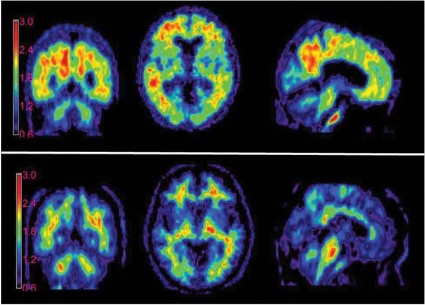

Courtesy Avid Radiopharmaceuticals

Medicare coverage for amyloid brain imaging could be reduced due to what some experts call a lack of evidence that beta-amyloid imaging with positron emission tomography (PET) improves outcomes for patients with Alzheimer’s disease.